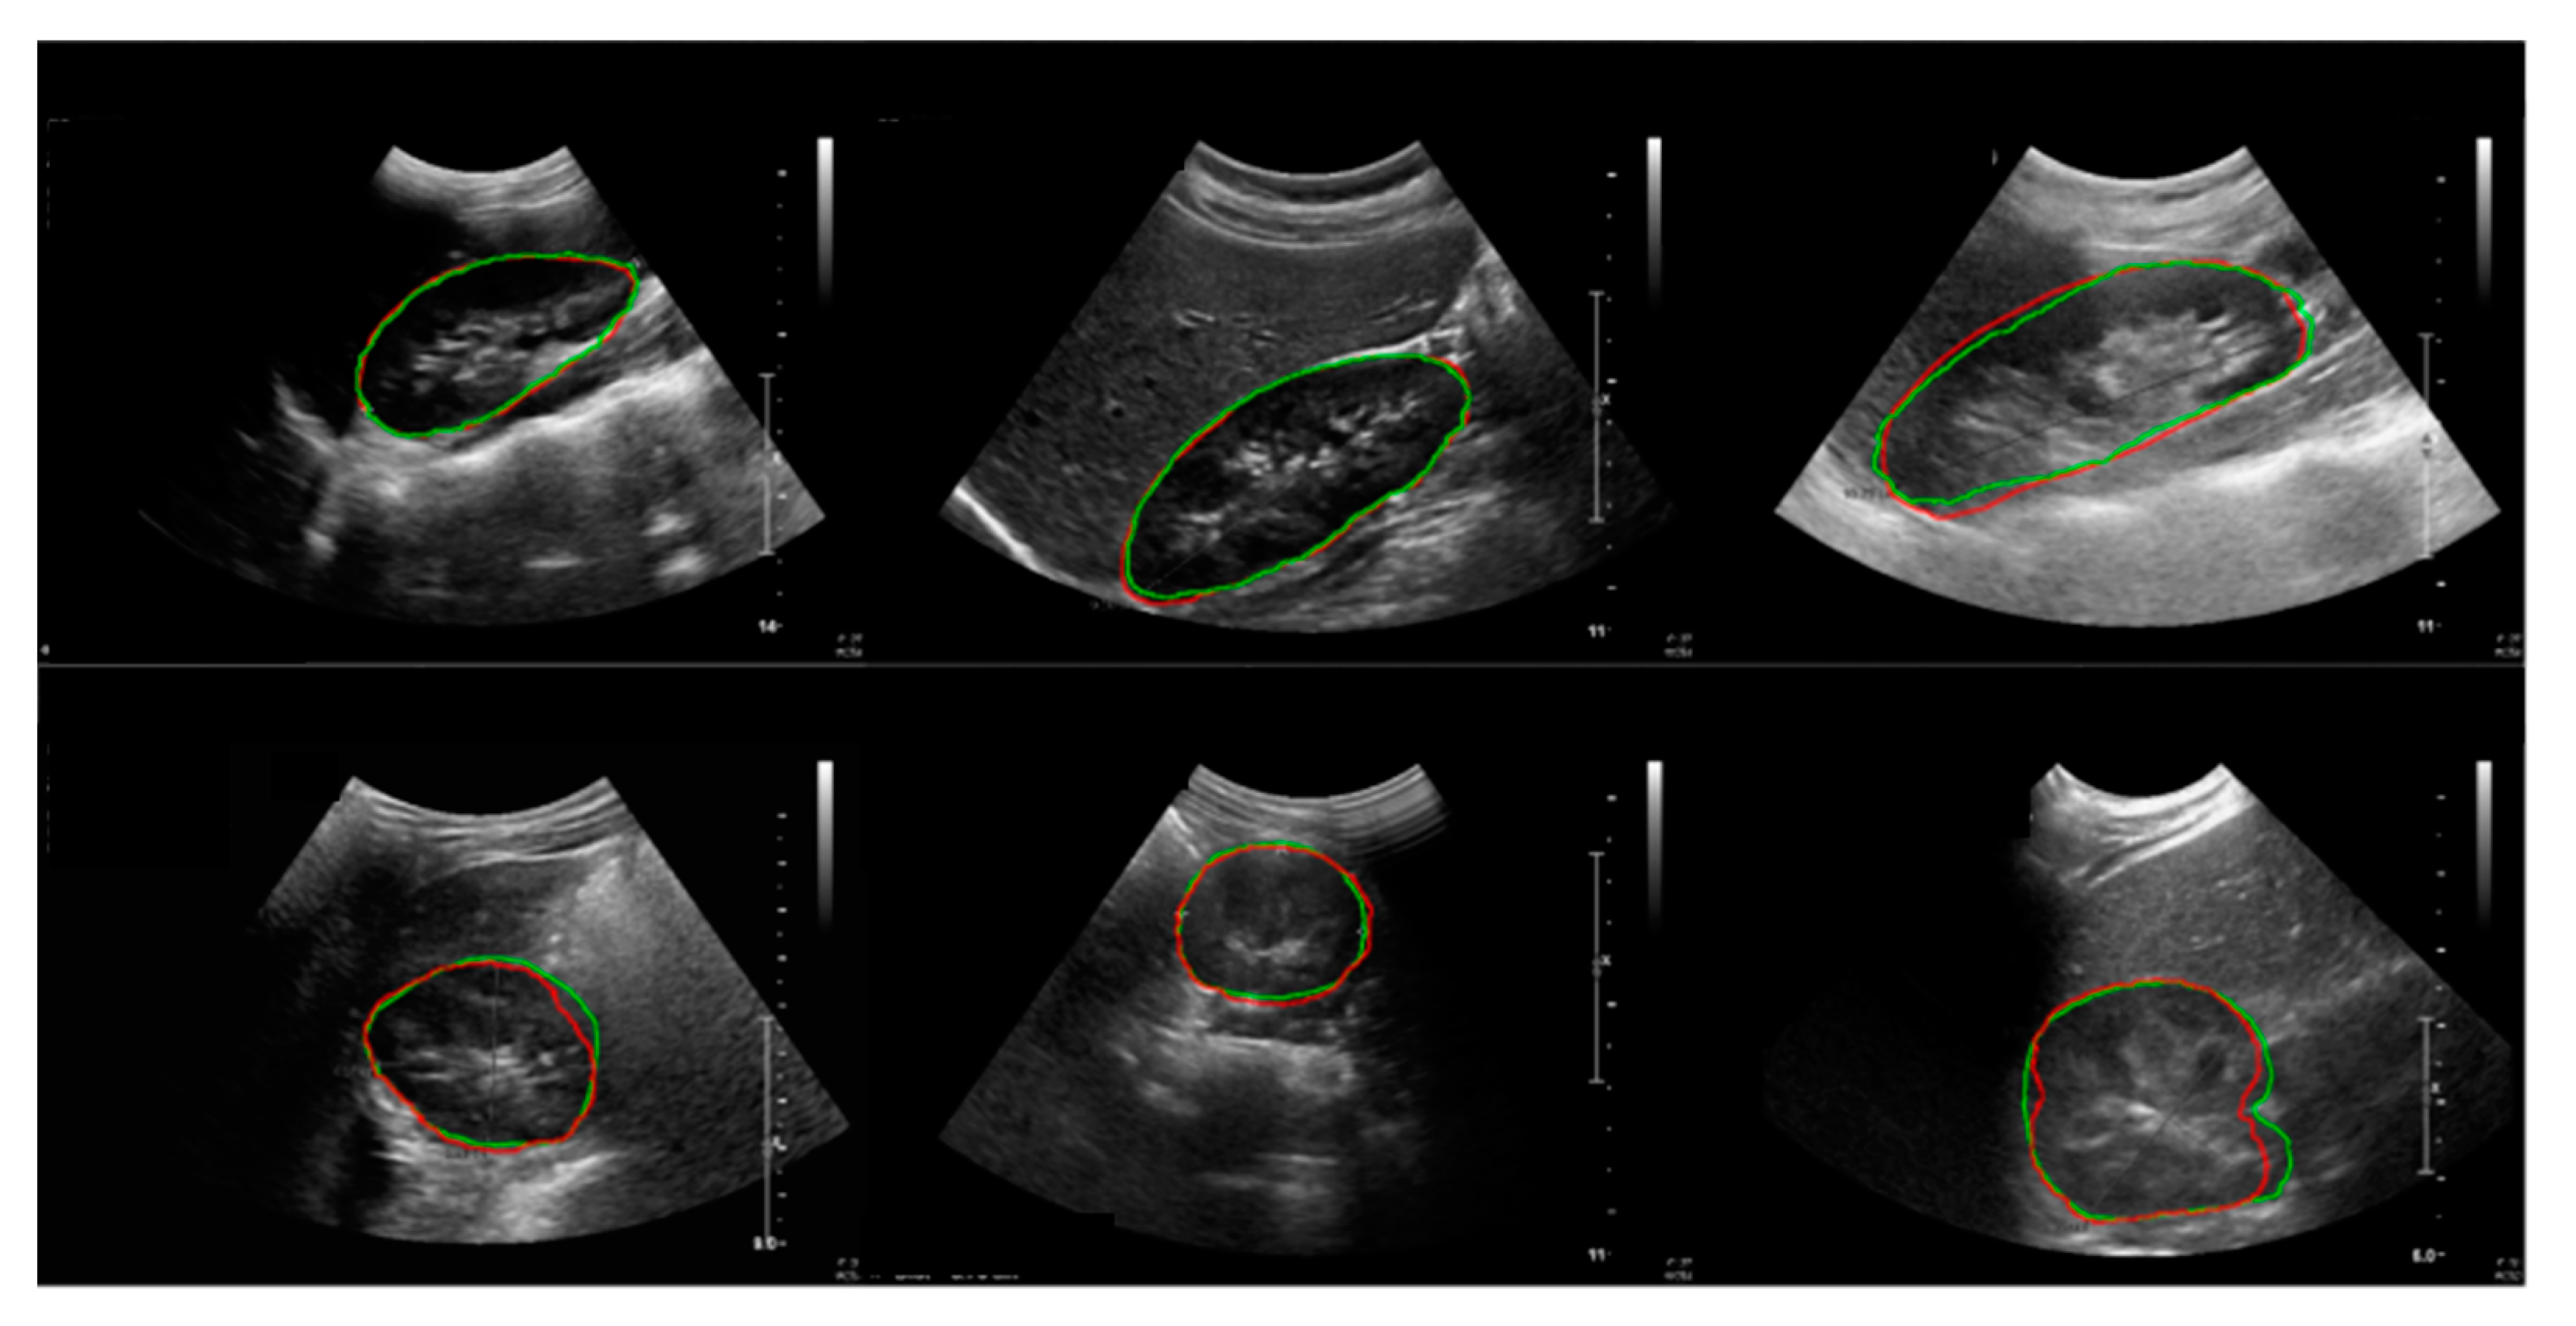

The results of the child kidney segmentation were evaluated qualitatively, as shown in Figure 8. The segmented outlines of the kidney images of the ground truth and deep learning results show good accordance on the coronal and transverse planes.

Figure 8.

Results of the kidney segmentation. Red line: model prediction; green line: ground truth. First row: coronal plane; second row: transverse plane.